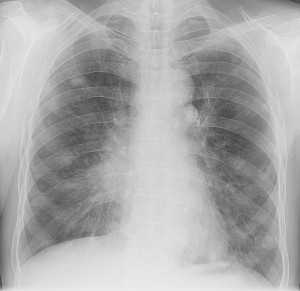

Гематогенные метастазы саркомы мягких тканей бедра на КТ (справа) и рентгенограмме (слева).

Обратите внимание на увеличение и нарушение структуры корня правого легкого. Это центральный рак. Кроме того, выявлены очаговые тени в обоих легочных полях (гематогенное распространение), а также «лучи», идущие радиально от опухоли корня (лимфогенное распространение).